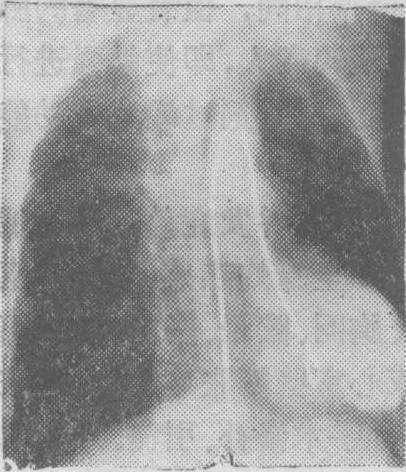

图1 瓣膜型肺动脉口狭窄选择性右心室造影侧位片

图示造影剂从右心室喷入肺动脉时呈细柱状影,肺总动脉呈明显的狭窄后扩张,状如动脉瘤。

图2 法乐四联症右心室造影(正位) 显示肺动脉与主动脉及其分支同时显影,右心室流出道狭窄。

(3) 右心室内: 在右心室流出道注射造影剂可显示漏斗部、肺动脉瓣和肺动脉狭窄(图1)。法乐四联症时在右心室注射造影剂可见主动脉及其分支无名动脉、颈动脉、锁骨下动脉和右心室流出道、肺动脉瓣、肺动脉一起显影,可见肺动脉瓣和漏斗部的狭窄情况(图2)。心室间隔缺损有右至左分流时,可见造影剂从右心室进入左心室; 在只有左至右分流的病人,如注射压力高,且造影剂在心室舒张期注入时,则造影剂亦可能通过心室间隔缺损而由右心室扩散入左心室。艾生曼格综合征 (心室间隔缺损型、动脉导管未闭型与主动脉肺动脉间隔缺损型)、大血管错位、右心室双出口、肺动静脉瘘和肺动脉扩张等亦可在选择性右心室造影过程中得到显示。